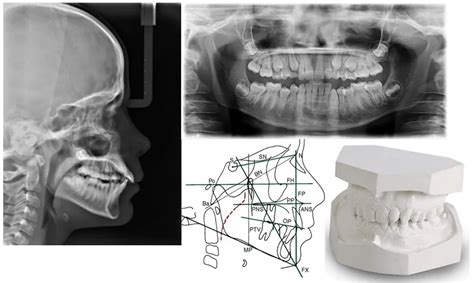

- Radiografías: lateral de cráneo y panorámica

- Toma de impresiones y confección de modelos de los dientes

- Análisis cefalométrico: la cefalometría es una técnica que permite obtener las medidas de los huesos del cráneo a partir de una radiografía lateral de cráneo y medir las distancias entre unos y otros para luego compararlos con patrones de normalidad. Es un procedimiento diagnóstico fundamental antes de iniciar un tratamiento de ortodoncia ya que permite determinar las anomalías morfológicas, de colocación y crecimiento de los huesos y dientes y así establecer el objetivo del tratamiento y realizar un adecuado seguimiento del mismo.

El software NEMOCEPH realiza los trazados cefalométricos de forma digital, incorpora una amplia gama de análisis cefalométricos y permite realizar superposiciones de los registros de cada paciente con el estándar, realizando la comparativa de los datos obtenidos en cada paciente con la norma e indicando el grado de desviación con la norma en cada valor de estudio. Es una herramienta muy precisa para el diagnóstico en ortodoncia y para la planificación de los tratamientos.

Superposición de fotografía sobre la cefalometría: permite visualizar la relación de los huesos con los tejidos blandos.

Análisis de los modelos: se realiza con el software NEMO CAST que permite visualizar los modelos de una forma conveniente: vista lateral, frontal, oclusal y de modelos articulados. El modelo convertido en archivo digital 3D se analiza virtualmente con la máxima precisión la forma y el tamaño de las arcadas del paciente, así como el tamaño y la posición de los dientes y el espacio disponible y necesario para su correcta posición y alineación.

La radiografía lateral del cráneo o cefalometría como su propio nombre indica se realiza de perfil para comprobar las proporciones del cráneo y que éstas sean las adecuadas. Por su parte, la ortopantomografía o radiografía panorámica es, en este caso, una radiografía frontal del paciente. En ella se toman imágenes de todas las piezas dentales pero también del cráneo, maxilares, etc.

Esta prueba es importante ya que gracias a ella podemos conocer el estado de las raíces de los dientes, el tejido óseo, las coronas… En definitiva, nos ofrece una información que a simple golpe de vista o pese a un estudio visual más pormenorizado no podrías ni tan siquiera vislumbrar.

Y por último, en un estudio de ortodoncia es fundamental la toma de modelos. Esto es una réplica a escala de la boca para poder ver con claridad las formas y las distancias. Una vez se obtienen todas las pruebas del paciente, los especialistas se reúnen, analizan estos ensayos y ponen en común que tratamiento de ortodoncia es mejor para cada caso en particular.